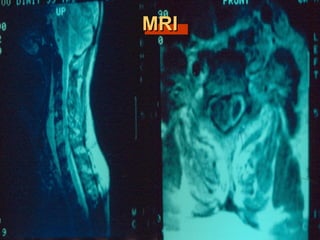

MRIMRI